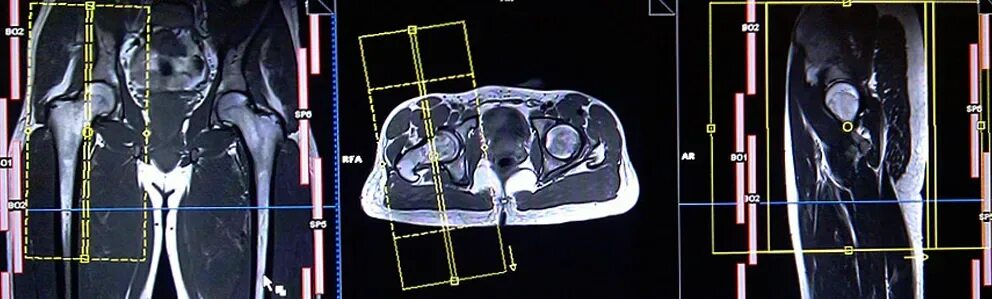

Bypass mrt